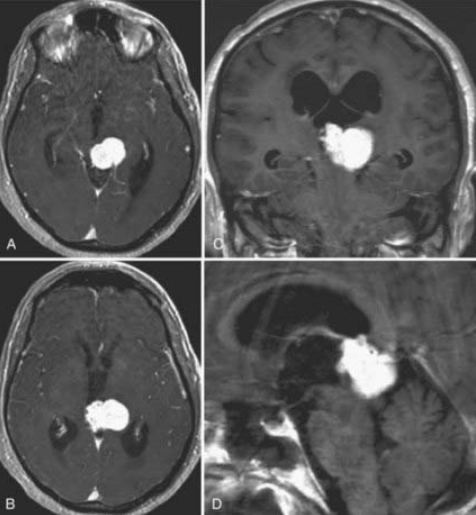

56岁男性,因持续加重的弥漫性头痛、眩晕、排尿障碍及顽固性呃逆就诊。影像学检查显示中脑顶盖区及第三脑室后部存在明显占位性病变。尽管该部位手术风险极高,毗邻重要神经核团和脑脊液循环通路,但考虑到患者症状进行性加重,神经外科团队最终决定实施肿瘤全切除术。术中运用先进的神经导航和实时电生理监测技术,成功在保护关键神经结构的前提下完成肿瘤全切。术后病理确诊为孤立性纤维瘤,随访显示患者症状完全缓解且未出现任何新增神经功能缺损。

术前MRI

术后MRI